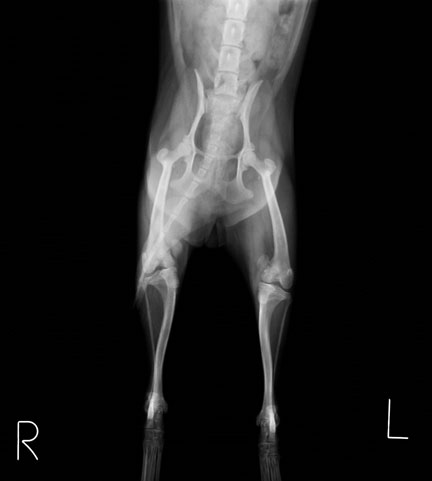

手術後レントゲン:膝蓋骨は正常な位置に整復され、足もまっすぐになりました。 術後は1週間程で歩行できるようになり、2ヶ月ほどでほぼ正常なワンちゃんと変わらず元気に遊べるようになりました。膝蓋骨内方脱臼は先天的疾患で、このワンちゃんほど重度な症例は珍しいですが、比較的小型犬に多い後肢の疾患です。膝蓋骨がすでに脱臼しているが症状が無いわんちゃんも多く認められます。安易な経過観察は関節炎や前十字靭帯断裂症など様々な合併症の原因となるため、比較的早期の整復手術をおすすめします!